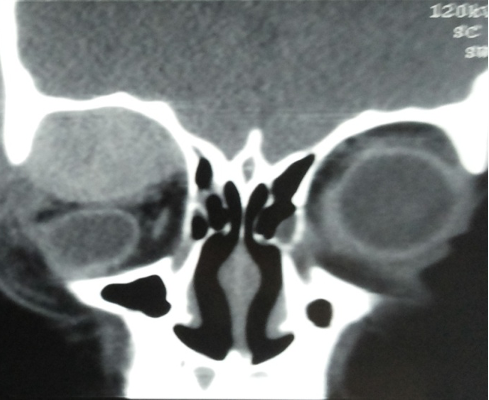

Coronal non contrast CT of right orbit showing well defined high attenuation sub periosteal hematoma indenting and displacing the globe inferiorly.